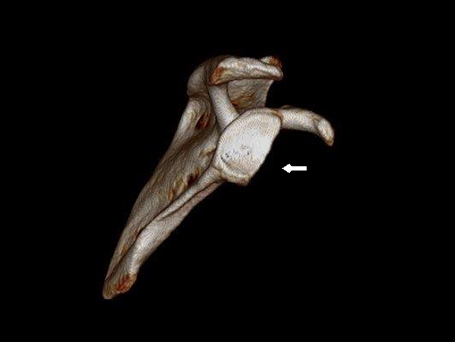

34 Jährige Patientin mit chronischer rechter Schulterinstabilität nach vorne unten. Bei der Analyse des Gelenkes fand sich in der 3D Schichtbilduntersuchung ein knöcherner Defekt (12% des Durchmessers) am vorderen unteren Pfannenrand. Operatives Vorgehen mit Spanaufbau des Defektes vom gleichseitigen Beckenkamm und Kapselstabilisation. Der Span wurde mit bioresorbierbaren Schrauben fixiert. Nach 3 Monaten bereits sehr gutes stabiles Bewegungsbild bei eingeheiltem Span. Noch Kraftaufbau erforderlich.

VORDERE CHRONISCHE SCHULTERINSTABILITÄT – KNÖCHERNER DEFEKT

Knöcherner Defekt am unteren Pfannenrand

Knöcherner Defekt durch Span ausgeglichen